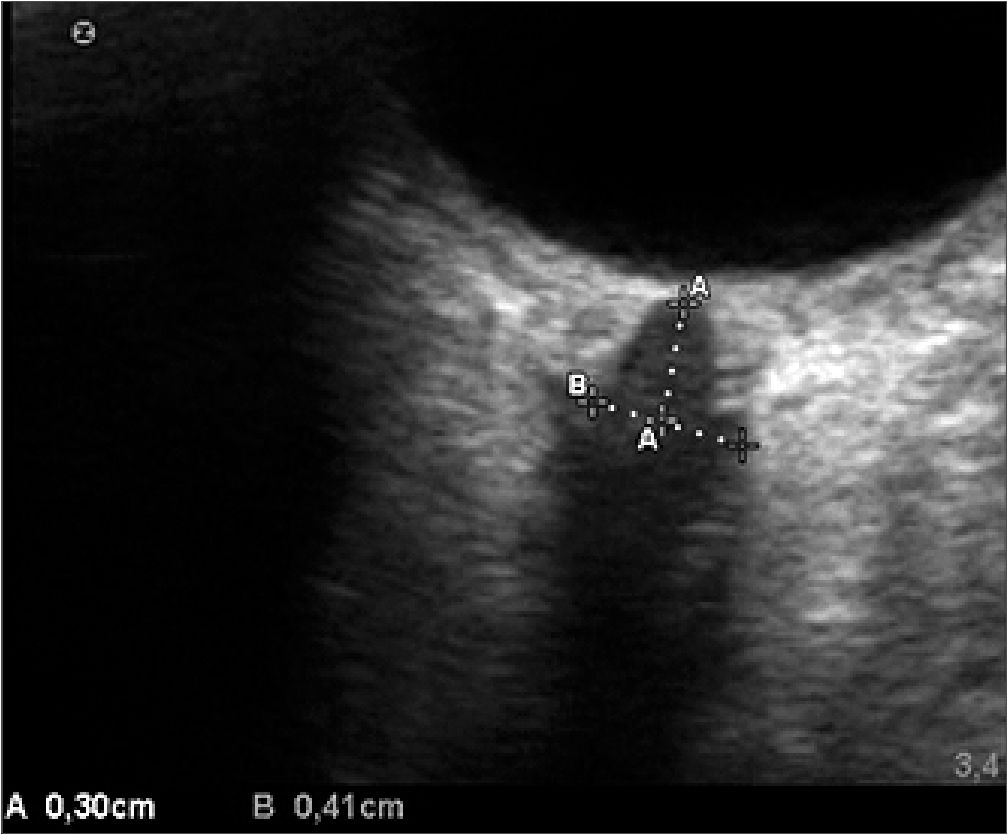

Dicha medición se realizó tanto en el plano sagital como en el axial del globo ocular; de ellas, se determino la mejor imagen, la cual fue definida como aquella con una visualización adecuada de la entrada del nervio óptico al globo ocular, los límites de la VNO y el nervio óptico. Esta se congeló, y se midió el DVNO 3 mm detrás del globo ocular a lo largo del eje perpendicular al disco óptico (Figuras 1 y 2).

Figura 2. Medición de la VNO.